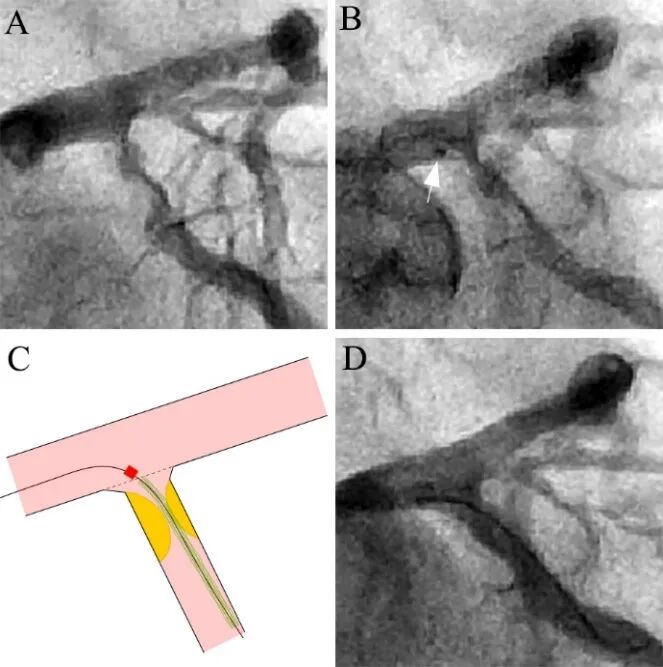

本例回旋支开口严重狭窄有两个特点(A):其一,成角接近90°;其二,起始部呈喇叭形,IVUS证实开口无明显斑块;因此适合精确定位技术。支架定位时将标志点(marker)定位于左主干轮廓内,此时支架刚好平开口位置(B)。C为示意图,注意标志点和支架近段存在一定间隙。最后结果良好(D)。

图8 回旋支开口精确定位。